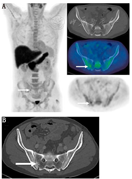

1.骨显像(包括SPECT和SPECT/CT)。用99Tcm标记的二膦酸盐进行骨显像始于20世纪70年代,这类显像剂在血液和软组织中清除速度快,注射后2 h即可采集到有良好对比度的图像[23]。尽管其数十年来被广泛用于检出和监测骨转移,但可供选择的现代影像技术具有更优的灵敏度和特异性[5,6,16,18]。然而,SPECT断层和SPECT/CT融合显像技术的出现,延长了骨显像的"寿命"。这些硬件和重建方法既提高了检测的灵敏度(更好的对比分辨率),又提高了检测的特异性(可显示与CT解剖相关的三维数据)[24,25]。结合CT形态学特征可提高骨显像的特异性,更准确描述放射性浓聚点的良恶性,增加对扫描结果解释准确性的信心,同时减少了模棱两可的结论(图1)[25]。

4.68Ga-PSMA PET/CT。由于PSMA显像剂能显示骨髓活性,所以对表达PSMA的骨转移而言,68Ga-PSMA显像的优势比18F-胆碱更明显(图5)[22]。一些研究表明,对前列腺癌骨转移,68Ga-PSMA PET/CT显像比骨显像具有更高的灵敏度[57,58,59],其与18F-fluoride PET/CT显像灵敏度相近,甚至更优[57,60]。这些研究结果表明,如果已进行PSMA PET/CT显像,则大多数前腺癌患者不需要再行其他骨特异性显像[58,59,60]。然而,另有一项研究表明,在计划进行放疗的晚期前列腺癌患者中,PSMA PET/CT显像对骨转移检出的灵敏度较低[61]。这些患者以前接受过常规治疗,上述18F-胆碱与18F-fluoride显像比较时所描述的肿瘤异质性反应[62]使得某些骨转移瘤的肿瘤细胞处于代谢静止状态(PSMA显像阴性),但仍具有持续的成骨细胞修复活性(18F-fluoride显像阳性)。